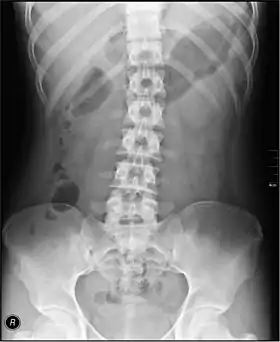

Abdominal x-ray

An abdominal x-ray is an x-ray of the abdomen. It is sometimes abbreviated to AXR, or KUB (for kidneys, ureters, and urinary bladder).

The standard abdominal X-ray protocol is usually a single anteroposterior projection in supine position.[3] Special projections include a PA prone, lateral decubitus, upright AP, and lateral cross-table (with the patient supine). A minimal acute obstructive series (for the purpose of ruling out small bowel obstruction) includes two views: typically, a supine view and an upright view (which are sufficient to detect air-fluid levels), although a lateral decubitus could be substituted for the upright.

Coverage on the x-ray should include from the top of the Liver (or diaphragm) to the pubic symphysis. The abdominal organs included on the xray are the liver, spleen, stomach, intestines, pancreas, kidneys, and bladder.